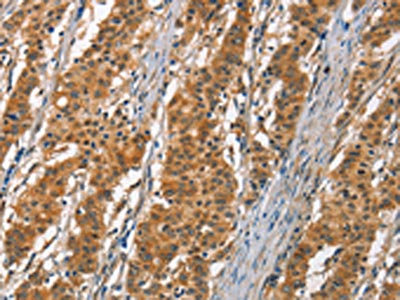

The image on the left is immunohistochemistry of paraffin-embedded Human gastric cancer tissue using CSB-PA274333(DKK3 Antibody) at dilution 1/30, on the right is treated with fusion protein. (Original magnification: ×200)